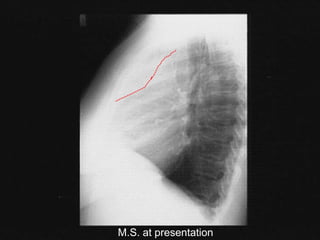

Case: M.S.

 25 year old woman

 persistent dry cough

 fever, NS, weight loss x 3 months

 left cervical lymphadenopathy (2 cm)

 left supraclavicular node (2 cm)

 no splenomegaly

M.S. at presentation

 CT scan: L supraclavicular adenopathy; large

mediastinal mass; R hilum; no disease below

diaphragm

 nodular sclerosis HD

 stage IIB

 with bulky mediastinal mass